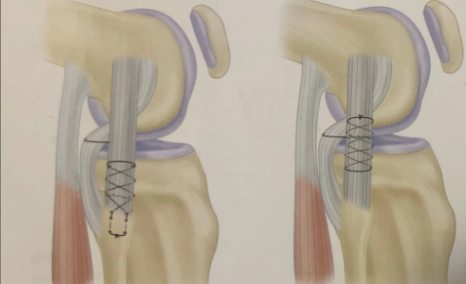

1.在撕裂相應(yīng)位置入路顯露撕裂部位;

2.松解剝離周圍軟組織;

3.自髂脛束股骨外側(cè)髁處分離至Gerdy結(jié)節(jié),形成一束帶;

4.用非可吸收縫線加強(qiáng)縫合至止點撕裂處,近端止點撕裂也可使用股二頭肌腱加強(qiáng)縫合,如長度不夠可適當(dāng)前移止點位置,錨釘打入皮質(zhì)后縫線將殘端及加強(qiáng)物重疊縫合。

德康Crius -聚醚醚酮帶線錨釘系統(tǒng)

產(chǎn)品規(guī)格:

4.5mm*14mm 5.5mm*15mm